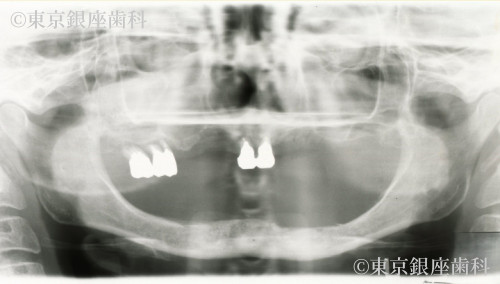

過去のインプラントで十分な結果が得られず再チャレンジし噛む機能を取り戻した60歳代女性の症例

Before

以前のインプラントが不十分で再治療を希望。下顎から先にインプラント、上顎洞炎治療後に上顎も実施。難症例ながら最終的に噛める状態を獲得。

上下ワンデイインプラント(再チャレンジ症例)